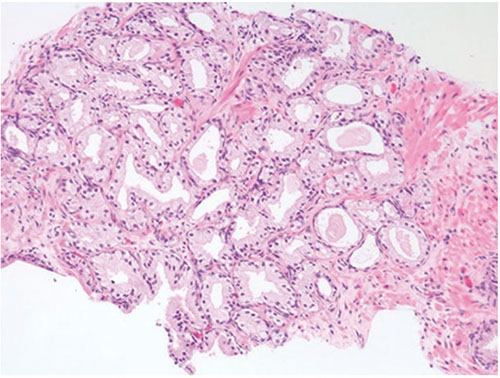

Clear Cell Cribriform Hyperplasia

Typically seen in the transition zone (vs HG-PIN in peripheral zone) has crowded cribriform glands c clear cytoplasm, sometimes growing as a nodule and in other instances more diffusely

- key distinguishing feature from HG-PIN is the lack of nuclear atypia, and at least some of the glands have a basal cell layer (not seen in HG-PIN)

- immunostaining for abs to basal cells not very helpful since both clear cell cribriform hyperplasia and HG-PIN have patchy basal cell layers

Occurs in transition zone, mostly in TURP for urinary obstructive sx and rarely needle bx

- some consider it a cribriform variant of BPH

- made of numerous cribriform glands separated from each other by modest amt of stroma in pattern of nodular hyperplasia

- if florid, can infiltrate stroma diffusely and have back-to-back glands

- if misdiagnosed, would be Gleason 4+4=8

Micro: epithelial cells have clear cytoplasm and small bland nuclei c inconspicuous or small nucleoli

- around man of the glands is a strikingly prominent basal cell layer c row of cuboidal darkly stained cells beneath the clear cells

- basal cells may form small knots at the periphery of some of the glands

- basal cells can occasionally have small nucleoli

- basal layer may also be inconspicuous or incomplete

- although usually unnecessary, HMWK stains basal cells

Distinguishing bwt clear cell cribriform hyperplasia and cribriform PIN can be difficult

- easier to diff from ca, which doesn't have basal cells

- clear cell cribriform hyperplasia probably unrelated to AC